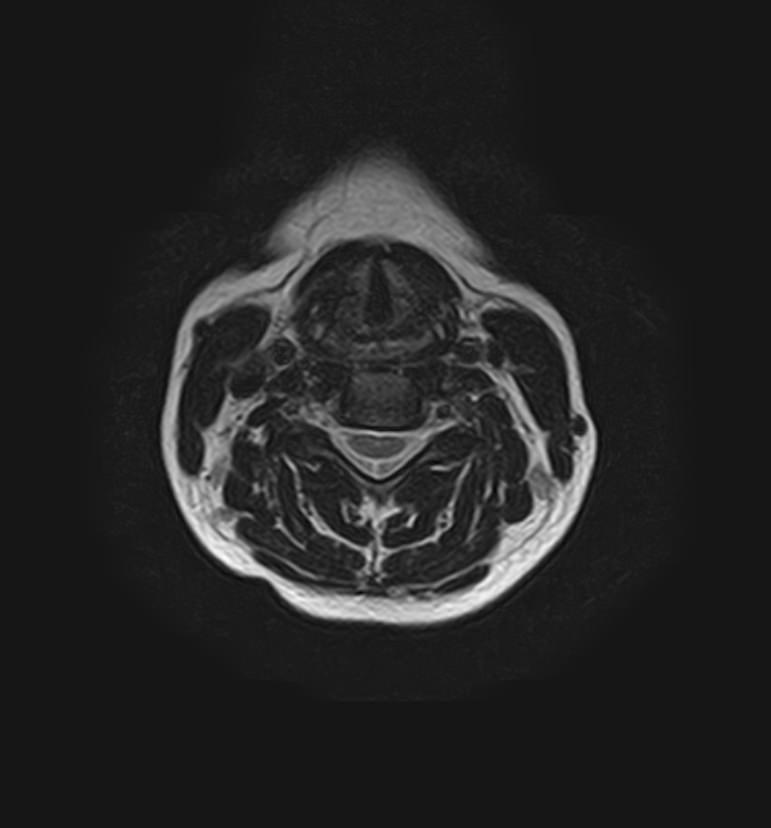

Для того, чтобы оценить состояние шейных позвонков с прилегающими тканями и одновременно визуализировать крупные сосуды шеи, в нашей клинике выполняется комплексное обследование, включающее два протокола: МРТ шейного отдела позвоночника и МР-ангиографию шеи.

В клинике «Доступная медицина» комплексное обследование шейного отдела позвоночника одновременно с МР-ангиографией шеи проводится на новейшем высокопольном томографе экспертного уровня TOSHIBA VANTAGE TITAN 1,5 Тесла, который производит послойное сканирование исследуемой зоны в разных плоскостях, затем при помощи компьютерных программ преобразует полученные данные в трехмерные изображения шейного отдела позвоночника и кровеносной системы, что позволяет проводить точную диагностику и назначать пациенту своевременное лечение.

Данное комплексное исследование позволяет проводить диагностику следующих патологических состояний:

• дегенеративно-дистрофические заболевания шейного отдела позвоночника (межпозвонковые грыжи, протрузии, остеохондроз, спондилоартроз, спондилез, унковертебральный артроз, сколиоз, усиленный или выпрямленный лордоз как нарушение статической функции позвоночника);

• травмы позвоночника, спинного мозга, связочного аппарата, близлежащих мягких тканей;

• опухоли спинного мозга, костей, нервных корешков или мягких тканей, окружающих позвоночник;

• инфекционные и воспалительные заболевания позвоночника и спинного мозга;

• демиелинизирующие заболевания спинного мозга;

• аномалии развития позвоночника;

• участки сужения, извитость, образование петель и перегибов сосудов;

• ангиомы, сосудистые мальформации.